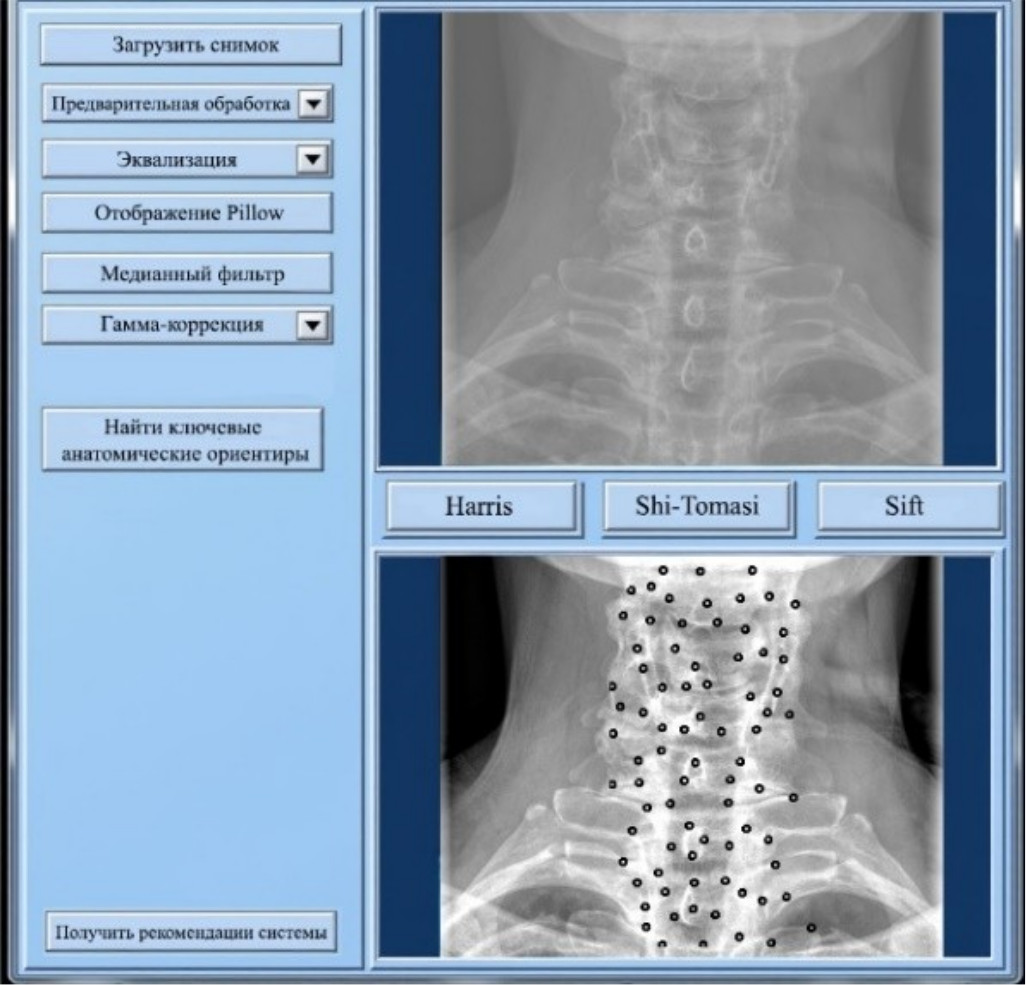

На рис. 9 представлены результаты работы системы поддержки принятия врачебных решений.

Рис. 9. Результаты работы системы поддержки принятия врачебных решений

Система включает в себя следующие ключевые возможности:

- автоматическая предварительная обработка медицинских изображений. Система использует метод стандартной эквализации, который показал наилучшие результаты по точности распознавания анатомических ориентиров;

- кластеризация и распознавание анатомических ориентиров. Алгоритм Shi-Tomasi применяется для выделения ключевых элементов позвоночника на изображениях, сгруппированных в 5–6 кластеров. Точность распознавания достигает 95 %;

- интеллектуальная система поддержки диагностики. На основе выделенных анатомических ориентиров система может предложить врачу предварительные диагнозы, а также рекомендации по дальнейшему обследованию пациента.

Таким образом, данная система упрощает процессы диагностики заболеваний позвоночника, а также облегчает работу медицинского персонала.